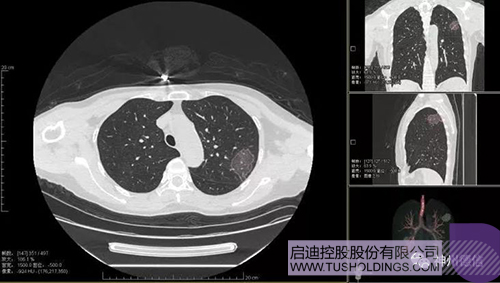

神州德信新冠肺炎检测及智能量化分析系统

mk电竞战略投资企业神州德信作为国内领先的肺部影像人工智能企业,针对新型冠状病毒肺炎开发了智能检测及量化分析系统,并在陕西、重庆等地定点医院投入使用。该系统在疑似病例大规模快速筛查及精准诊断方面发挥了重要作用,特别是其具有的肺炎患者临床影像跟踪量化随访功能,为快速有效阻断疫情扩散提供了有力武器。